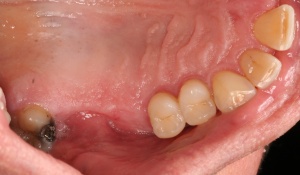

In der präimplantologisch chirurgischen Phase ist darauf zu achten, dass möglichst viel Knochen bei einer Osteotomie erhalten bleibt. Die labiale/bukkale Knochenlamelle genießt besonderen Schutz. Häufig macht es Sinn, den Zeitpunkt einer Extraktion bzw. einer Osteotomie sowie deren Technik mit dem implantierenden Kollegen abzustimmen oder diese auch durch den Implanteur selbst vornehmen zu lassen (Abb. 4).

Eine weichgewebschirurgische Vorbereitung des zukünftigen Implantatlagers bereits zu diesem Zeitpunkt ist häufig ratsam. Dazu gehört unter anderem wie in diesem Bildbeispiel die Verbreiterung der Zone keratinisierter Gingiva. Eine gedeckte Einheilung des Implantates wird somit wahrscheinlicher. Therapeutisch kompliziertere Eingriffe nach der Freilegung oder sogar erst nach prothetischer Versorgung werden vermieden (Abb. 5a/b).